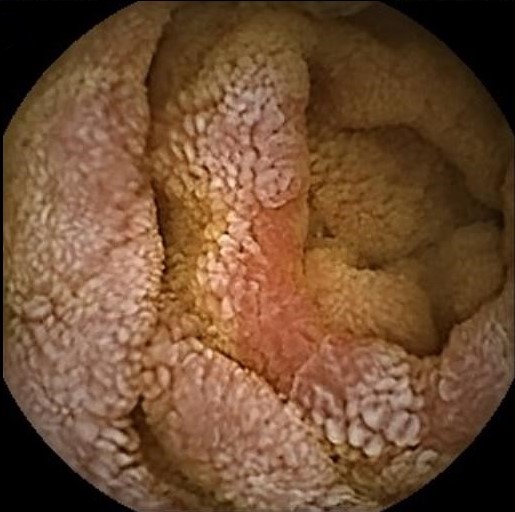

A challenging case of chronic diarrhea

Isabel Garrido, Armando Peixoto, Hélder Cardoso, Guilherme Macedo

Serviço de Gastrenterologia, Centro Hospitalar Universitário de São João

A 74-year-old Caucasian woman, without relevant past medical history, was admitted due to weight loss, abdominal pain and diarrhea for a year. Blood tests showed severe hydroelectrolytic and nutritional disorders. Upper endoscopy and colonoscopy had no relevant changes. Capsule endoscopy revealed extensively scattered lymphangiectasias, areas with shortened villi and some erosions in the jejunum and ileum. The histological examination showed severe mucosal atrophy, crypt hyperplasia and lymphoplasmacytic infiltration in the lamina propria, without significant intraepithelial lymphocytosis. Towards the diagnosis of autoimmune enteropathy, treatment with corticosteroids was started, with a quick improvement of symptoms and nutritional deficits.